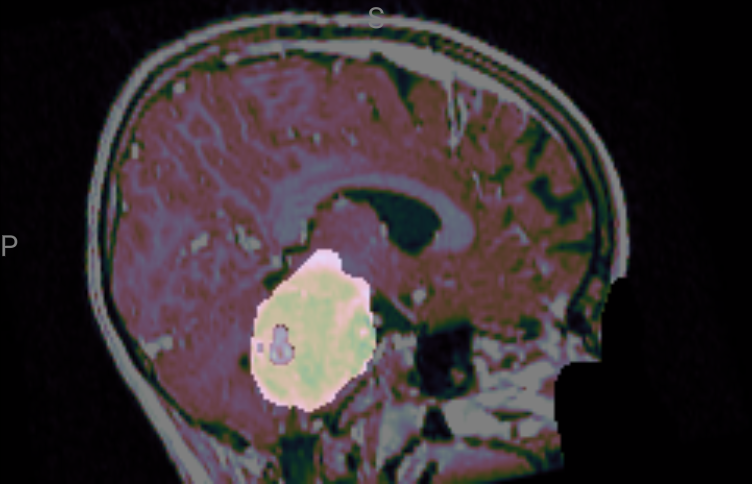

These results demonstrate great performance across all critical tumor cystic component (CC), peritumoral edema (ED), enhancing tumor (ET), non-enhancing tumor (NET), tumor core (TC), and whole tumor (WT). In Fig. 8, we present a representative example in which our model delivers highly accurate lesion segmentation, clearly illustrating its precise predictive capabilities.

Refer to caption

(a) Sagittal of case 381.

(b) Coronal of case 381.

(c) Axial of case 381.

Figure 8: BraTS_PED_00381

ET: 0.9575 NET: 0.9722 TC: 0.9749 WT: 0.9749